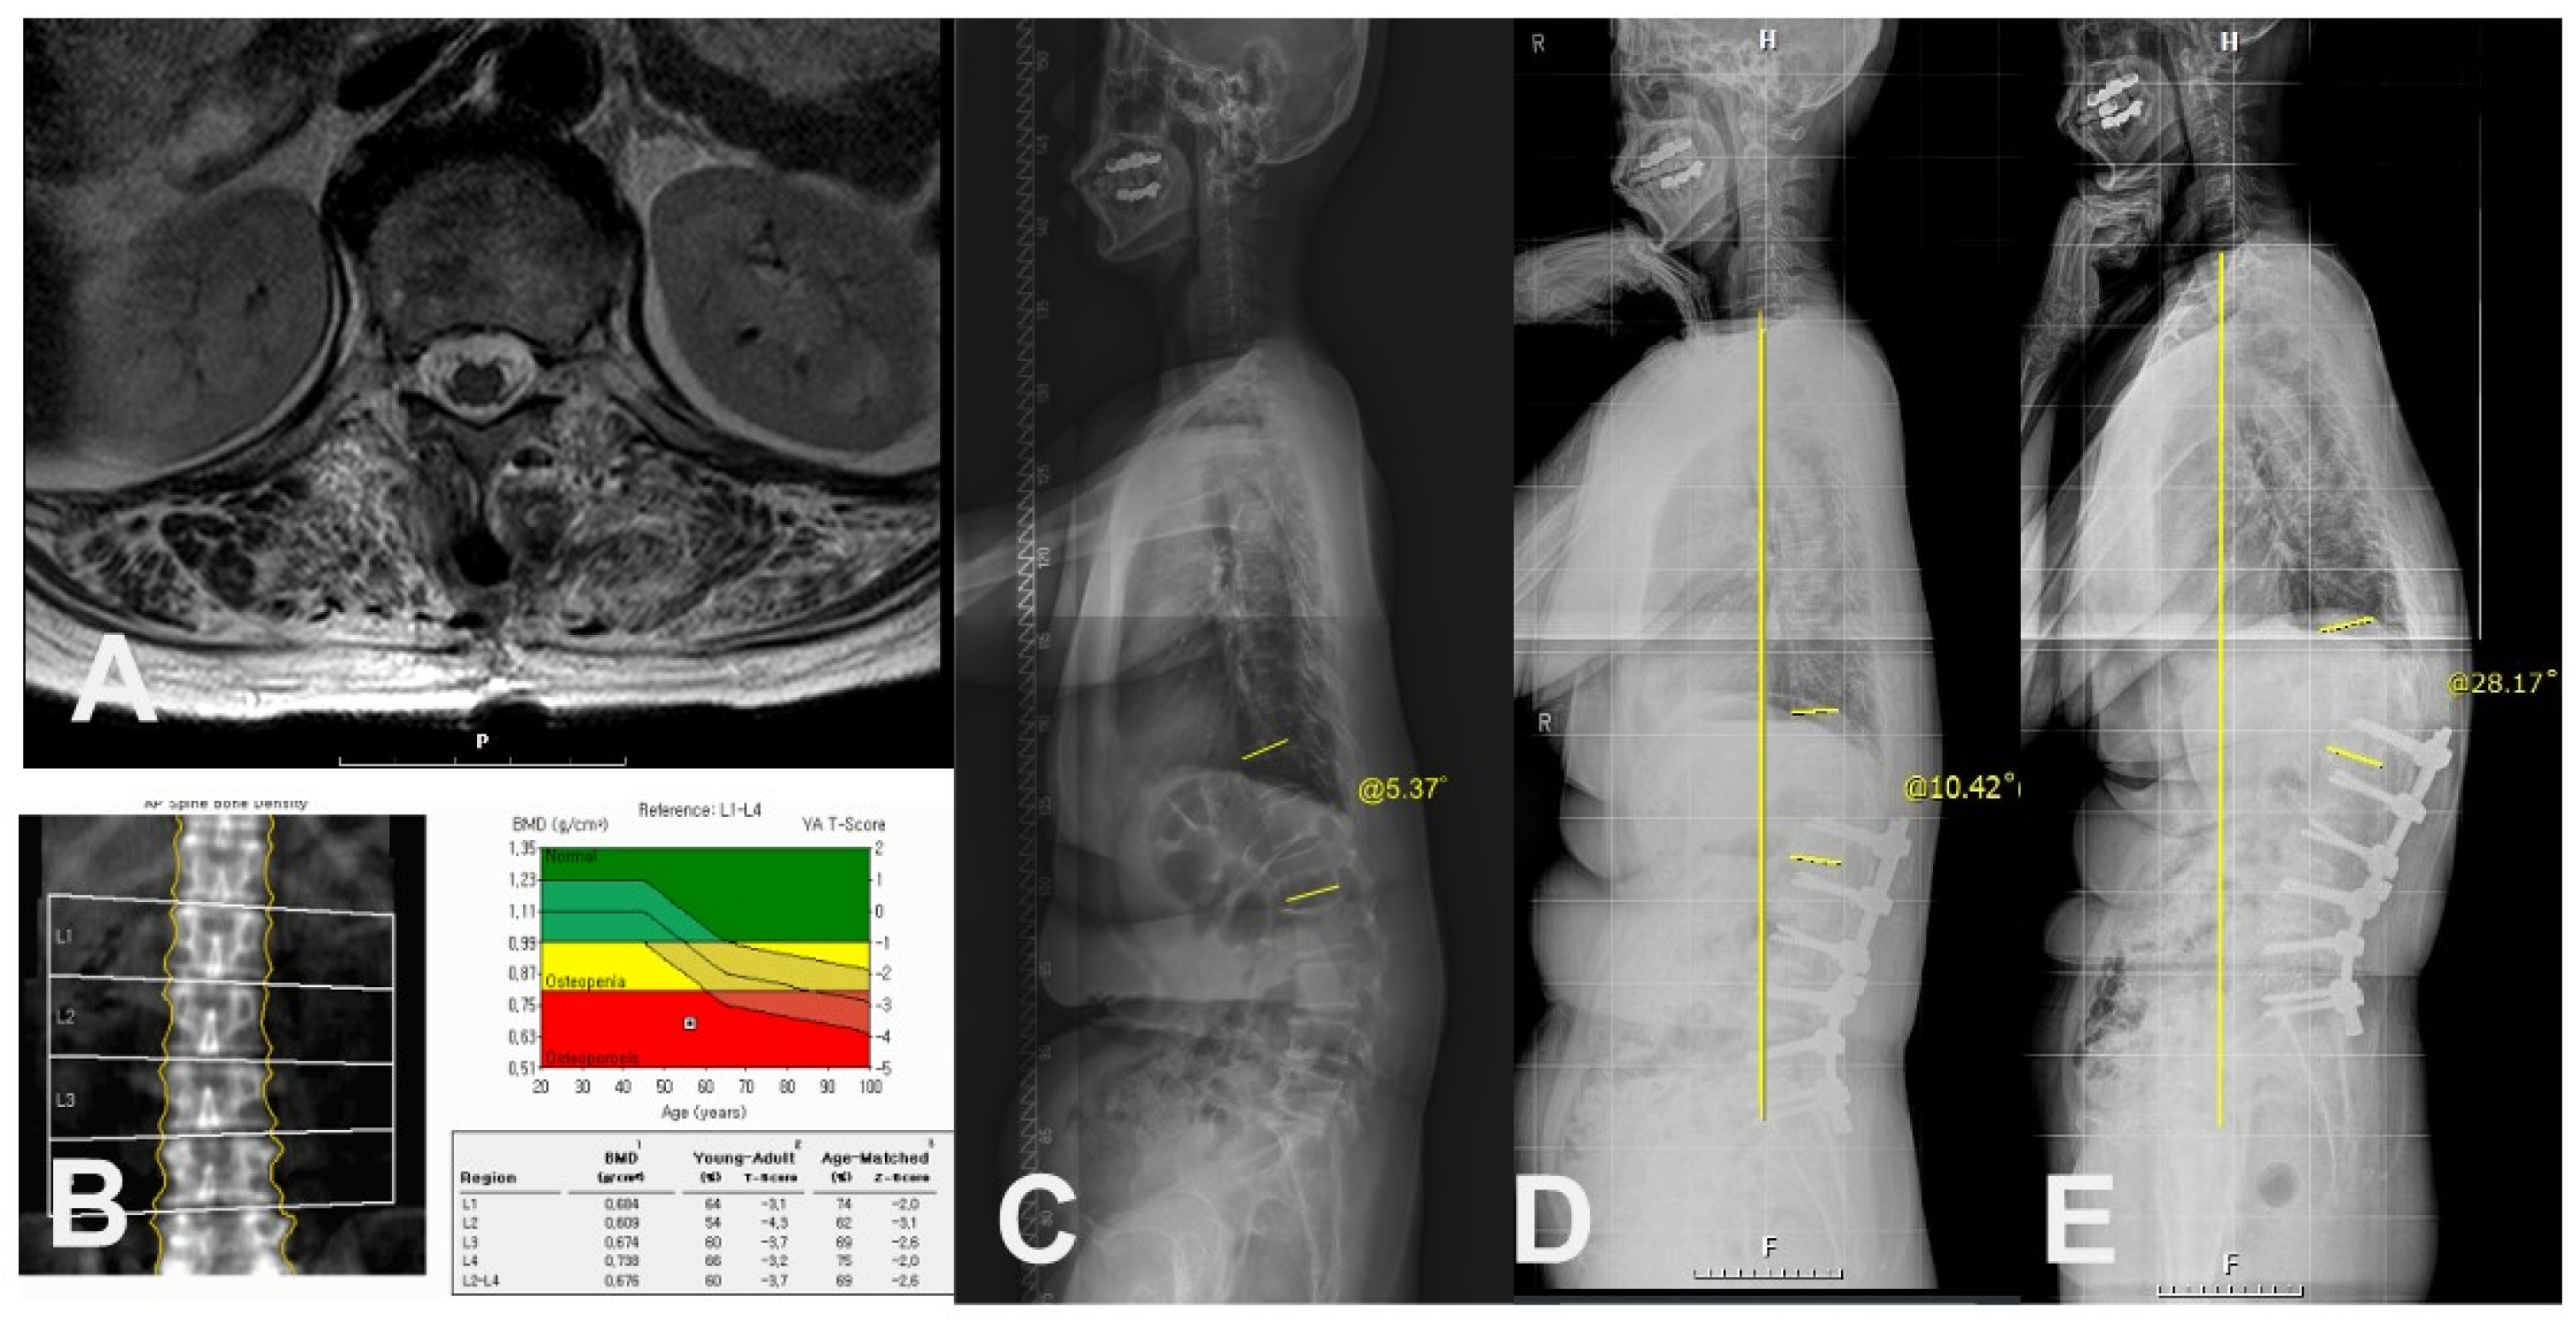

Figure 4.

Case of 66-year-old female patient with PJK. (A) Preoperative axial T2-weighted magnetic resonance image showing erector spinae muscle with severe (>50%) fat infiltration at T12-L1 level. (B) Preoperative BMD showing osteoporosis. (C) Preoperative whole spine standing lateral radiograph showing PJA of 5.37°. (D) Postoperative 3-month standing lateral whole spine radiograph showing PJA of 10.42°. (E) Postoperative 2-year standing lateral whole spine radiograph showing PJK (PJA of 28.17°) with increased C7SVA.